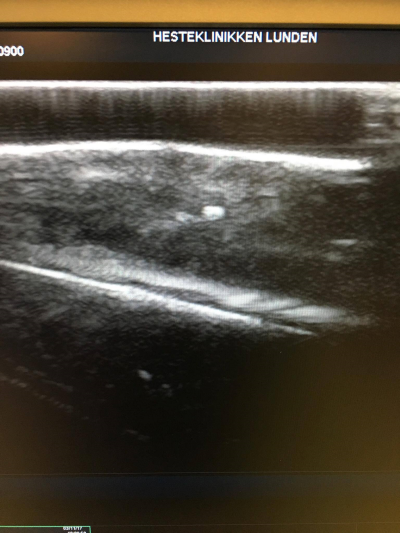

Da dette kun hjalp lidt blev benet bรฅde scannet og rรธntgen fotograferet, og der fandt vi noget sรฅ usรฆdvanligt som et par smรฅsten fra banebelรฆgningen,ย der var hamret dybt ind i sรฅrkanalen.

Med nedenstรฅende rรธntgenfotos ses tydeligt de to smรฅsten, der sad inde i benet pรฅ Belle Reine.